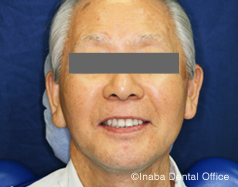

口元の若返りについて 歯がないせいか、口元が老けて見えます。入れ歯治療を受けようと決心しましたが、口元も若返りますか?

歯を失うと上下の唇は内側に入り込みます。口元のたるみやしわも目立つようになり、ほうれい線も深くなります。入れ歯を装着することで、唇の厚みが増し、口元のたるみやしわを改善できることが多いです。

きれいな前歯を選びたい 新しく入れ歯を作ろうと思っています。いままでは歯医者さんにおまかせでしたが、前歯の見た目や歯の色を自分で選ぶことはできますか?

患者様ご自身で前歯の形や色調を選ぶことは可能です。前歯の重なりをつけて、よりディテールを加えることもあります。

前歯の見え方 笑っても前歯が唇で隠れているため、コンプレックスを感じています。女優さんのように、笑ったときに白いきれいな歯に見えるような入れ歯にできますか?

前歯の位置は、基本的には天然歯も人工歯も同じ考えです。少し専門的になりますが、切歯乳頭から7mm前方に中切歯の切縁を排列したり、赤唇粘膜移行部に中切歯の切縁が軽く接触するように排列するなど、審美の法則に従った人工歯の排列方法があります。

歯の色調は患者様の好みに合わせられます。当院では、白い歯をご希望の場合、ヨーロッパから取り寄せることもあります。